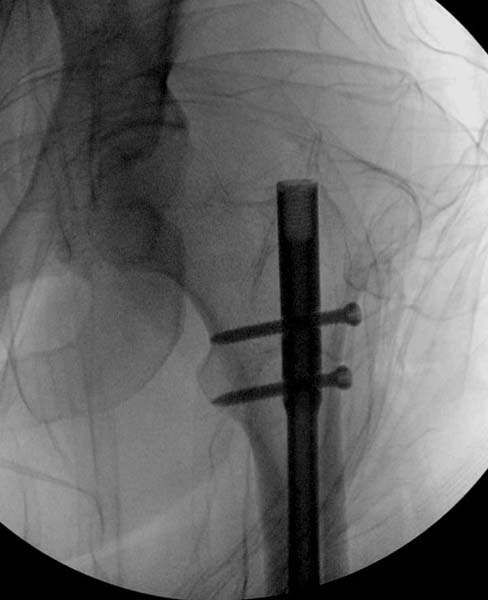

Около 11.00 вечера больная переведена в реанимацию, без сознания, но стабильная.. На третьий день провели стабилизацию перелома бедра антеградным остеосинтезом.

Закрытый БИОС решает множественные проблемы связанные с лечением переломов, но проблема дистальной блокировки без рентгена до сих пор остается нерешенной. Рекламированные производителями приспособления для дистальной блокировки из-за различной кривизны кости не эффективны или стоит очень дорого (Smith&Nephew SureLock). Задержка операции из-за блокировки не всегда удовлетворяет, и многих вынуждает искать альтернативные методы фиксации. С результатами таких действий, остеомиелитом и несращениями, встречаемся в ежедневной жизни..

Для решения проблемы дистальной блокировки компания DigiMed недавно предложила систему блокировки без рентгена. Пока в стране только два набора и только для антеградных гвоздей, но компания работает над созданием устроиства для других гвоздей тоже..

Результат первых случаев показала отсутствие разницы между занятиями на муляжах, а также Workshop и с удивительной точностью вывел латерально над кожей специальное сверло. Дальше по сверлу тонкий направитель и проводится сверление каннюлированным сверлом....